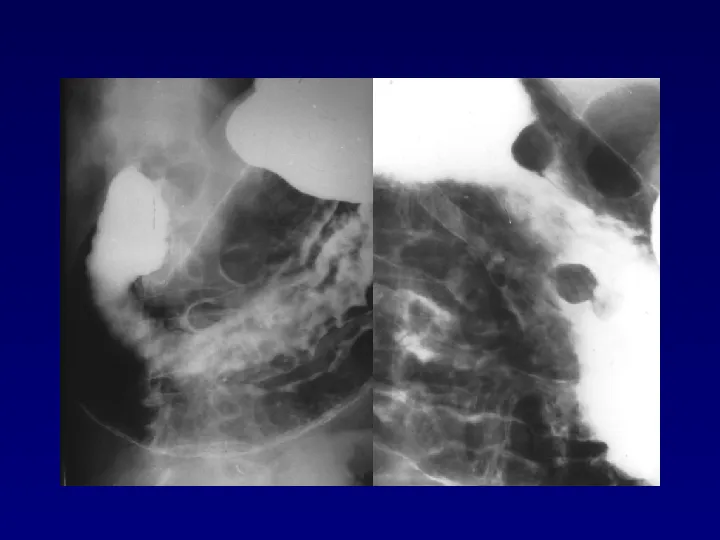

>【影像PPT】胃肠道钡餐检查的操作规范

【影像PPT】胃肠道钡餐检查的操作规范